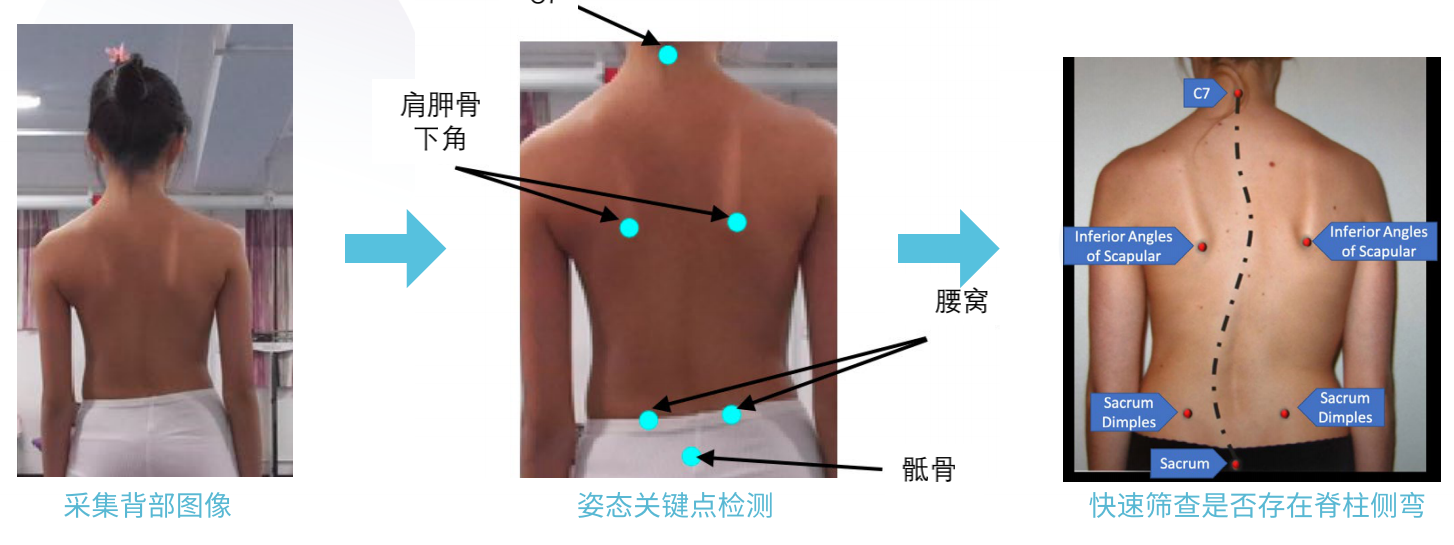

如何实现院外脊柱侧弯快速筛查?

利用人工智能深度神经网络结合医学影像处理技术,智能提取背部C7、肩胛骨下角、腰窝及骶骨六个姿态关键点,智能评估冠状面Cobb角度,实现脊柱侧弯快速筛查。